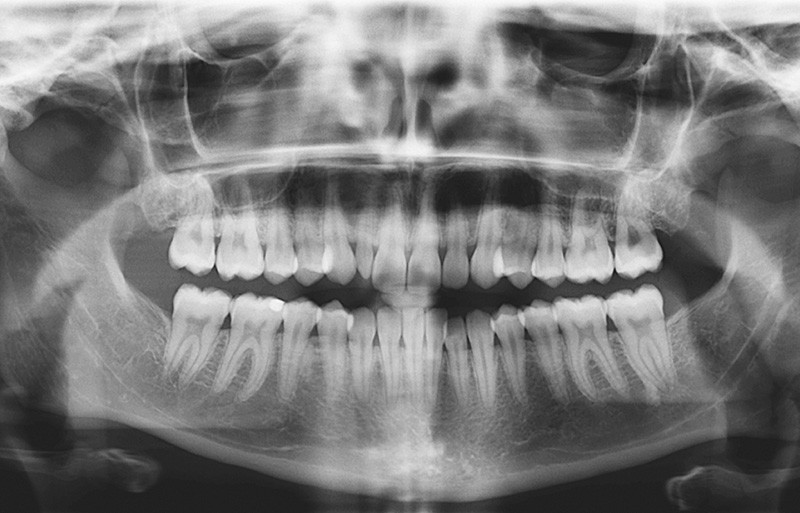

La radiographie panoramique révèle la présence de toutes les dents définitives, à l’exception des dents de sagesse, extraites (fig. 7).